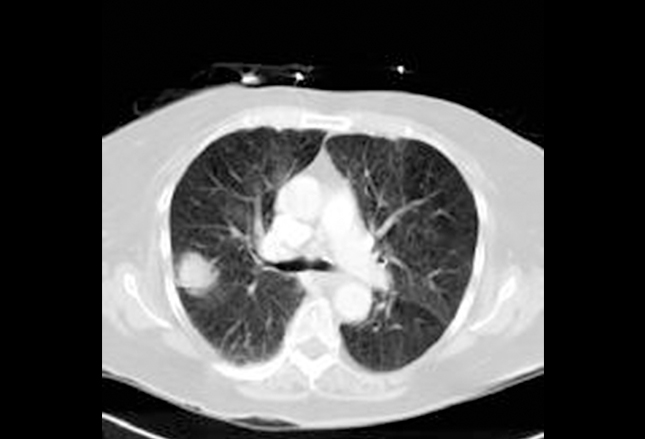

SCLC既能表现为中心性,也能表现为外周性。轴向CT为右肺外周性SCLC。